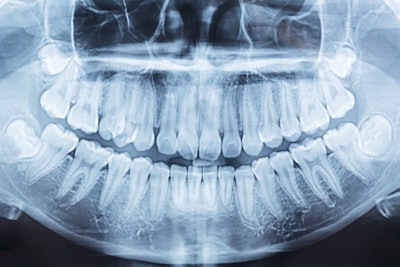

1. AAOMR: Stop shielding patients during dental imaging

In August, the AAOMR issued a position statement published in the Journal of the American Dental Association stating that it no longer recommended that patients’ reproductive organs and fetuses be covered during dental imaging. In the position statement, the AAOMR recommended that teams cease shielding patients’ thyroid and reproductive parts during intraoral, panoramic, cephalometric, and cone-beam computed tomography imaging, because lead aprons provide no protection from internal scattered radiation.